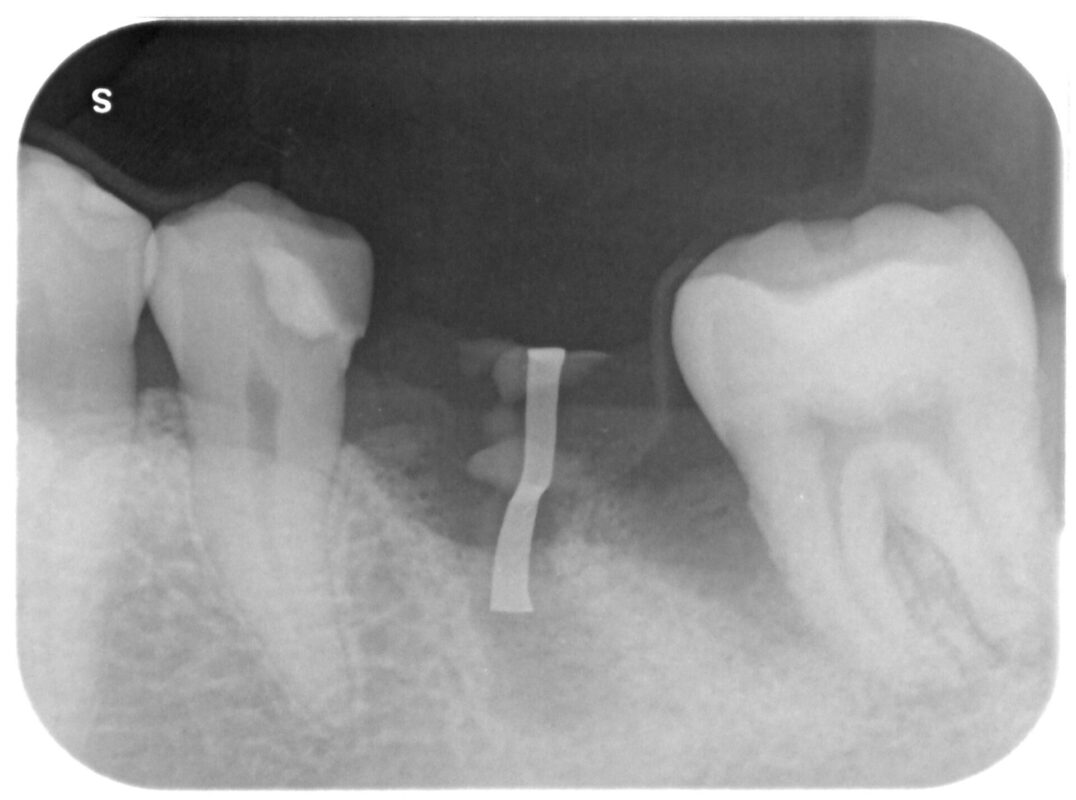

インプラント治療時

奥の骨欠損部に対してGBRを行っています。